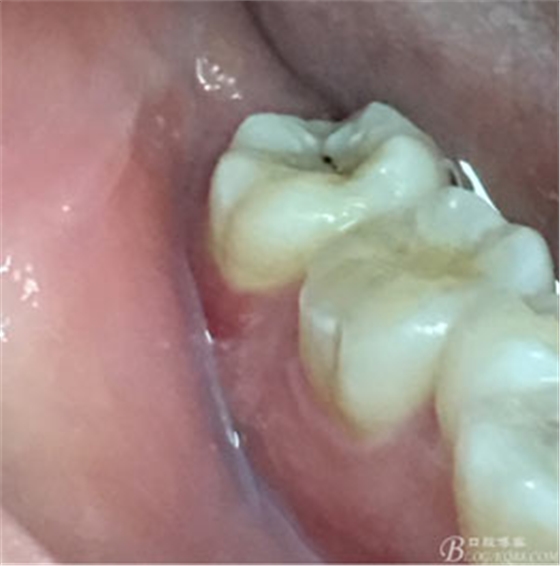

圖3.取出棉球口內(nèi)發(fā)現(xiàn)37合面有開髓孔,探針出血,頰側(cè)牙齦紅腫